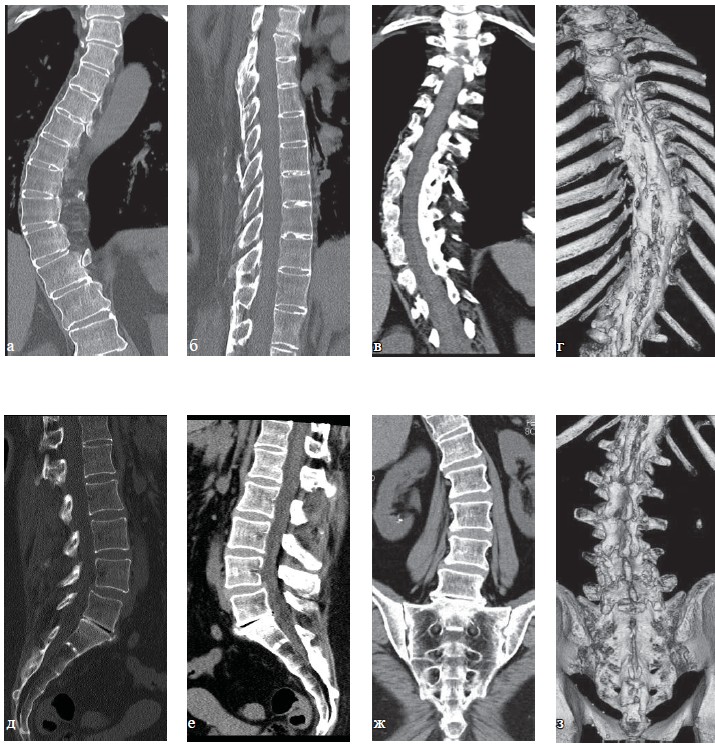

Рис. 2. Рентенография шейного отдела позвоночника, та же пациентка: а — прямая проекция; б — боковая, в — в положении максимального сгибания; г — в положении максимального разгибания. Определяются нарушение статики, начальные явления остеохондроза шейного отдела позвоночника (I степень).

Рис. 3. КТ поясничного отдела позвоночника, та же пациентка: а, б — аксиальная плоскость;

в, г — сагиттальная плоскость. Определяются остеохондроз поясничного отдела позвоночника I ст., спондилоартроз, передний спондилолистез позвонка L3 I ст.

Рис. 4. МРТ грудного отдела позвоночника, та же пациентка: а -Т1-ВИ; б, г, д — Т2-ВИ; в — Т2-ВИ с жироподавлением. Определяется остеохондроз грудного отдела позвоночника I ст., умеренное снижение высоты тел ТН6—ТН9, грыжи Шморля в краниальных и каудальных пластинках тел ТН6-ТН10, признаки перенесенной болезни Шейермана-Мау.